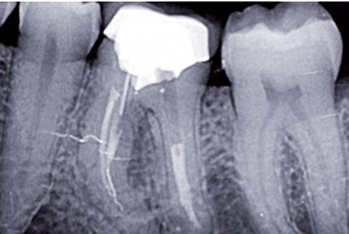

La consultation de dépistage des foyers infectieux bucco-dentaires doit s’appuyer sur une confrontation des données cliniques et radiographiques, prenant en compte le contexte médical spécifique du patient, afin de proposer la meilleure thérapeutique et la meilleure prévention possibles.